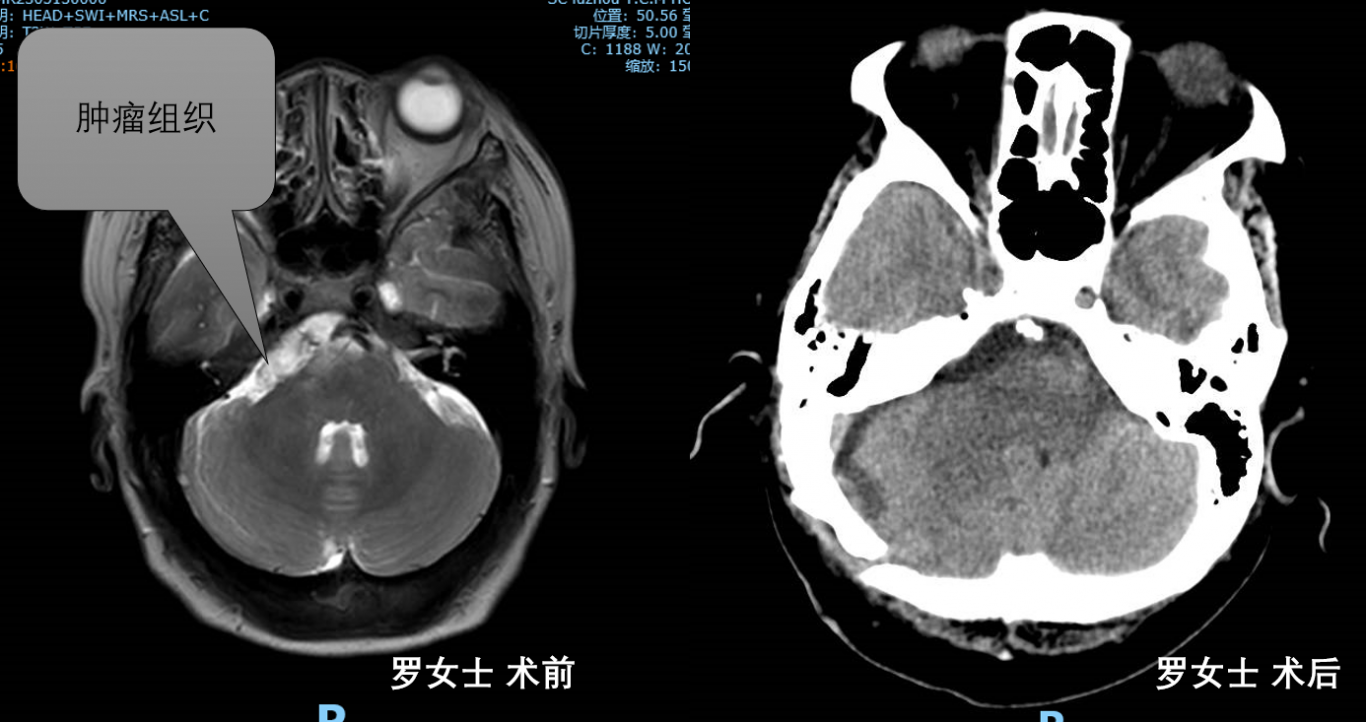

案例一:

叙永罗女士因反复不明原因咽部疼痛,反复多家医院就诊无缓解,后行头颅MRI提示脑干右侧占位性病变。术后病检提示表皮囊肿,术后2周患者便出院。